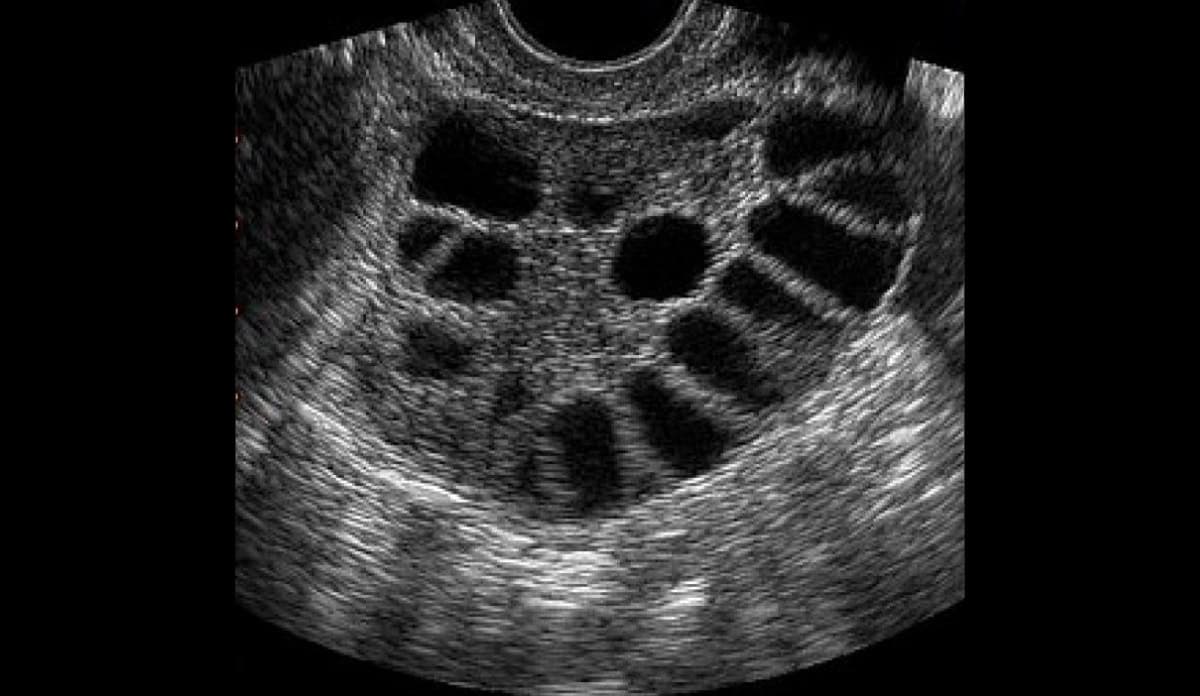

- The polycystic appearance of ovaries on ultrasound

Being diagnosed with polycystic ovarian syndrome does NOT mean you have many ovarian cysts or growths in your ovaries. It is merely a description of what your ovaries look like.

A polycystic ovary has multiple follicles (>12 follicles) while a normal ovary has an average of 5-6 follicles.

The appearance of these multiple follicles, together with the hormonal changes in your body, usually result in the symptoms that you experience with PCOS.